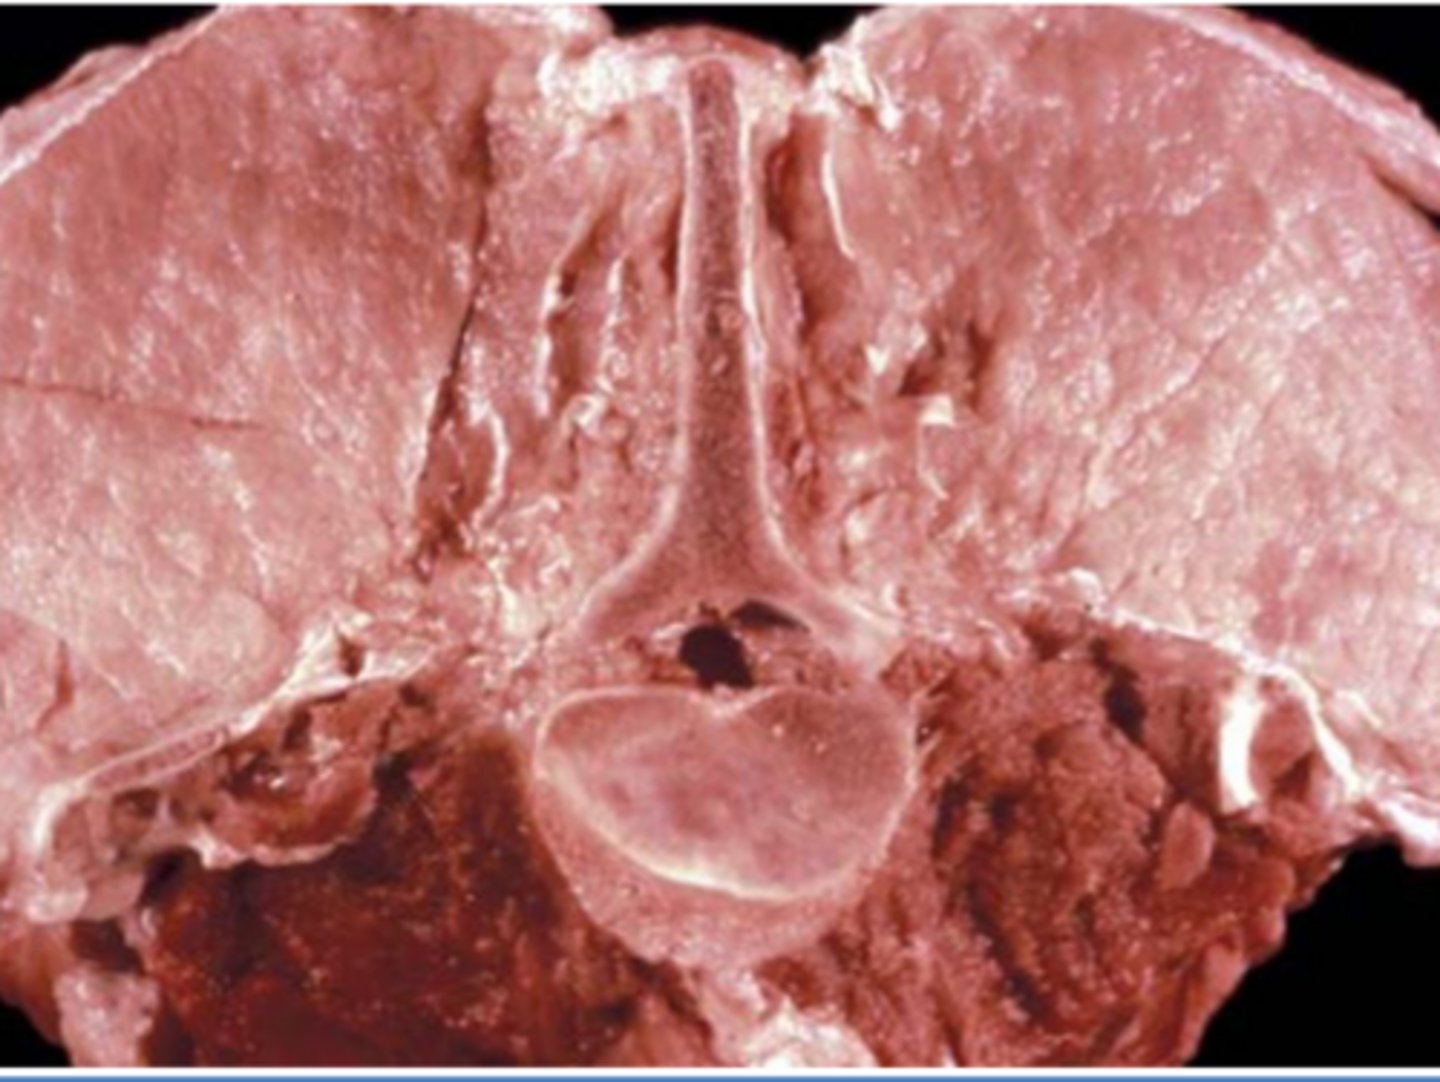

What is eosinophilic myositis?

A sarcocystis infection of cattle that leads to a hypersensitivity - green coloration of muscle